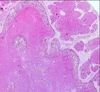

Name this lesion.

Proliferating trichilemmal cyst